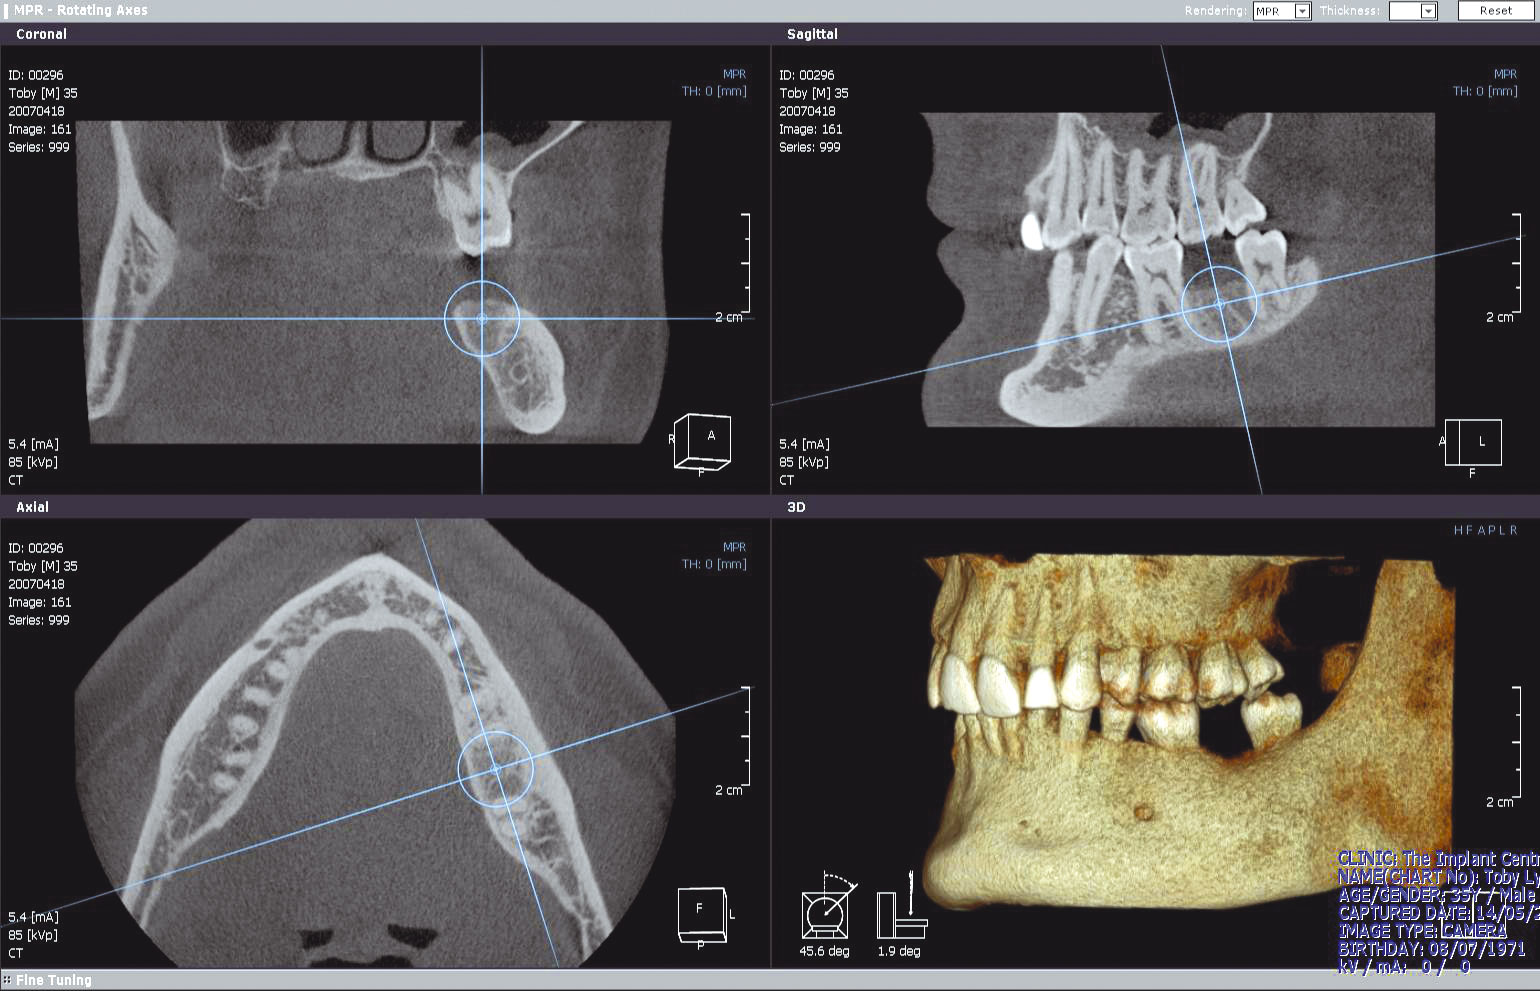

We are very proud to be the first practice in the South East to have a Cone Beam CT scanner. This state of the art machine allows us to obtain high resolution, 3-dimensional images of our patients’ jaws, at a fraction of the radiation dose of a conventional hospital CT scan.

Our scanner can image both jaws in just 15 seconds and at a dose of less than 3 OPGs, compared with a hospital-based scanner dose of about 20 OPGs!

The ability to determine precisely how much bone is available for the placement of implants is an enormous help when planning cases and the level of safety and predictability that this degree of planning provides is also hugely reassuring for the patients involved.

But we’re not just restricted to imaging your patients for implants – impacted teeth are ideal for imaging with a 3D scanner;

Chloe is a 13yr old girl with unerupted upper canines. It’s clear to see that these 3-dimensional images make her surgical and

orthodontic planning far easier and much more accurate.